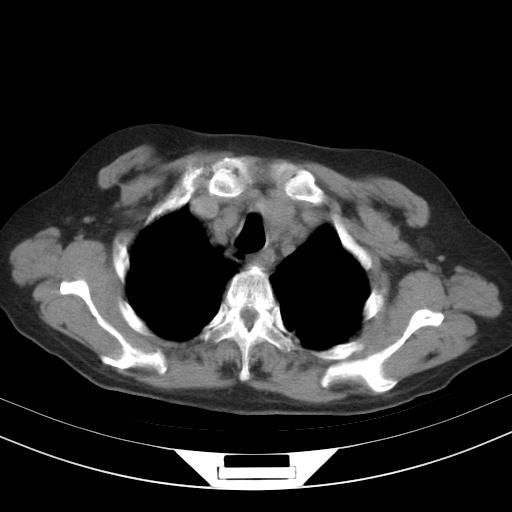

老年女性,嗜睡3天,意识模糊。轻咳,无发热。

1)两肺感染性病变;建议抗炎治疗后复查。2)纵隔淋巴结肿大。3)左侧胸腔积液。

2)纵隔淋巴结肿大。